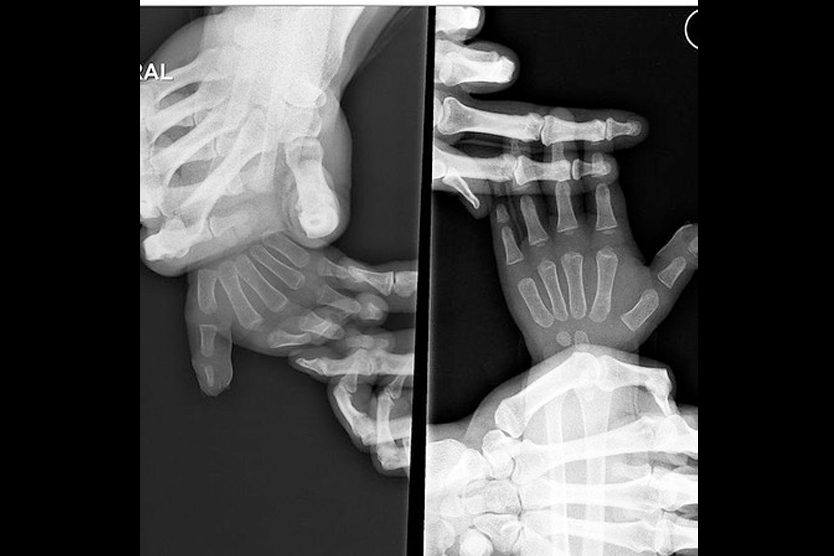

A recently installed art display outside the School of Medicine dean’s offices highlights the power of hands in this healing profession. The glossy photo installation on the second floor of the Medical Sciences building on the Parnassus campus was spearheaded by Sarah Paris, the school’s director of communications.

The 22 images selected for the display were captured in photo shoots across campus, including the Student Homeless Clinic, the Kanbar Center and the new Anatomy Learning Center. Students, staff, faculty and patients volunteered to have their hands photographed.

“When Sarah and I started the project, I was concerned that just focusing on hands would be too abstract in expressing what we were trying to convey,” Fall said. “What I found was that hands can express a great deal of intimacy. Whether it is in a lab or a clinic setting, the power of hands in healing and discovery is such a vital link.”